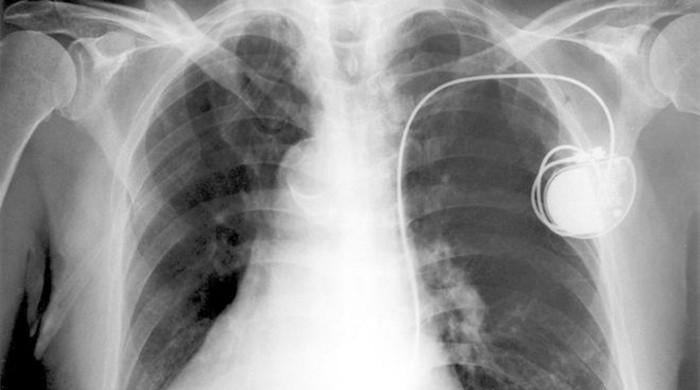

Pacemakers may fail to properly regulate patients’ heartbeats near certain appliances and tools that generate electric and magnetic fields, a German study suggests.

Researchers tested how electric and magnetic fields impact pacemakers, small battery-operated devices that help patients’ hearts beat in a regular rhythm, for 119 people under different conditions.